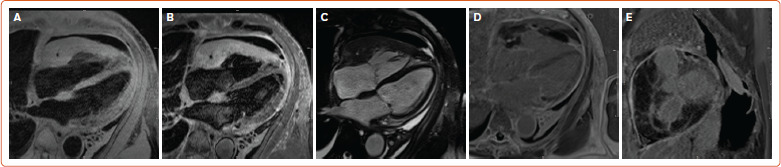

原发性心脏肿瘤仅占全部心脏肿瘤的0.3%;其中,淋巴瘤仅占所有原发性心脏肿瘤的2%。心脏淋巴瘤预后恶劣,由于诊断和治疗的延误,往往不到1年。心脏MRI是心脏肿瘤成像的金标准。我们描述了一个76岁的男性病例,没有明显的既往病史,他在心脏MRI上发现大量心包积液与心脏淋巴瘤一致,而组织诊断为原发性心脏弥漫性大b细胞淋巴瘤。本文回顾了心脏淋巴瘤的临床和影像学特点,并讨论了患者的治疗管理和副作用。

Primary cardiac tumors account for only 0.3% of all cardiac tumors; of these, lymphomas account for only 2% of all primary cardiac tumors. Cardiac lymphomas have a grim prognosis, often less than 1 year due to delays in diagnosis and treatment. Cardiac MRI is the gold standard for the imaging of cardiac tumors. We describe the case of a 76-year-old man with no significant past medical history who presented to the emergency department with a large pericardial effusion that was found to be consistent with cardiac lymphoma on cardiac MRI prior to tissue diagnosis of a primary cardiac diffuse large B-cell lymphoma. The clinical and radiological features of cardiac lymphoma are reviewed, and the therapeutic management and side-effects that the patient experienced are discussed.